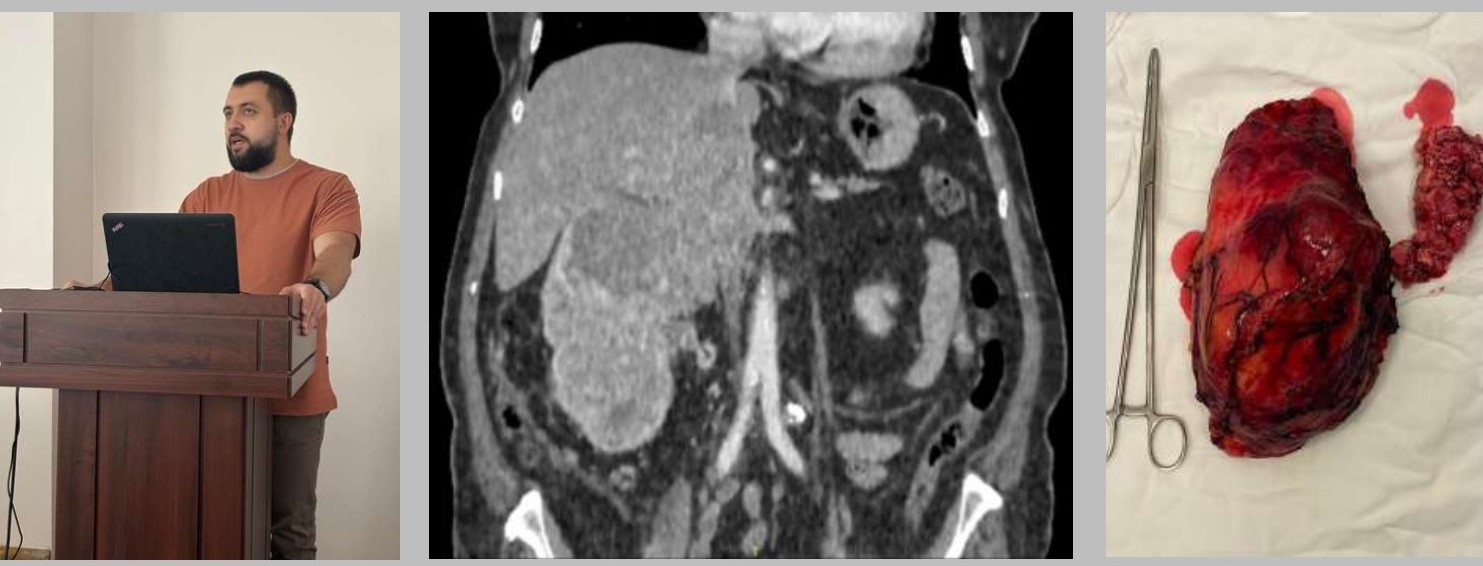

На компьюторной томограмме представлен внутрисосудистый рост опухоли по ходу почечной вены в нижнюю полую вену, встречается у 4-10% больных почечно-клеточным раком. Слева фотография удаленной почки с тромбом.

Врач онкоурологического отделения ОБУЗ «Курский онкологический научно-клинический центр имени Г.Е. Островерхова» Антонов Андрей Александрович представил доклад о текущем состоянии вопроса в Курской области относительно маршрутизации пациентов, применения современных методов диагностики и оперативного лечения. В рамках выступления доктор также поделился опытом проведения уникальных операций, осуществляемых на базе онкоурологического отделения данного медицинского учреждения.

Примером может служить лапароскопическая нефрэктомия с тромбэктомией из нижней полой вены. Тромб, сформировавшийся в просвете почечной или нижней полой вен, представляет собой фрагмент опухоли, распространившийся по сосудистому руслу. Единственным эффективным методом лечения является хирургическое иссечение опухолевого образования и тромба. Данный метод был детально рассмотрен в ходе презентации, основные этапы операции продемонстрированы в видеофрагментах.